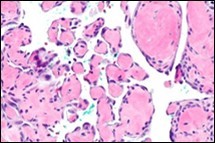

On microscopy, superficial squamous epithelial surface is intact. Sub-epithelial connective tissue stroma exhibits slit-like, vascular spaces. Upon extended magnification, multiple, intravascular papillary projections encompassed within a hyalinised stroma are discerned. Centroidal calcification appears in combination with intravascular, papillary endothelial cell proliferation, lined with singular layer of endothelial cells devoid of cytological atypia6, 7.

Characteristically, the vascular neoplasm denominates numerous papillae within blood vessels. Papillae are coated with singular or dual layer of flattened endothelial cells with an encompassing hyalinised, fibrous tissue core. Vascular lumen is distended with thrombosis. Foci of haemorrhage with fibrinous and purulent exudate are discerned. Tumour perimeter depicts inflammatory granulation tissue. Cholesterol clefts and focal reactive bone formation may concur. Extraneous squamous epithelium may be discontinuous and ulcerated. The neoplasm is devoid of features of malignancy4, 6.

Numerous micro-calcifications can be observed within the lesion which may engender vascular occlusion and tissue necrosis6. Figure 1, Figure 2, Figure 3, Figure 4, Figure 5, Figure 6, Figure 7, Figure 8.

Figure 1 Papillary endothelial hyperplasia elucidating papillary articulations layered with a single layer of endothelial cells and a commingling of fibrinous, thrombotic exudate 10.